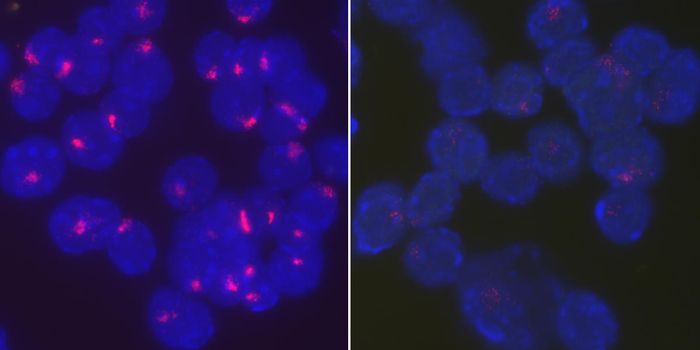

OCT 23, 2017ImmunologyWhy are women more likely to have an autoimmune disease? It may literally be in their genes. A new study suggests that w ...